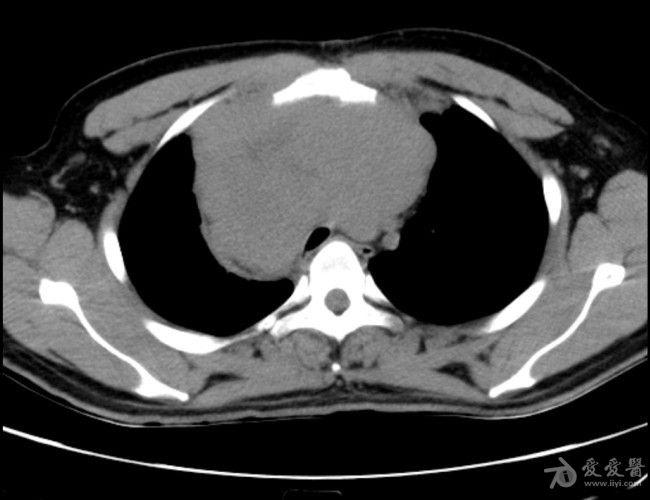

病例19恶性胸腺瘤

图片尺寸666x525